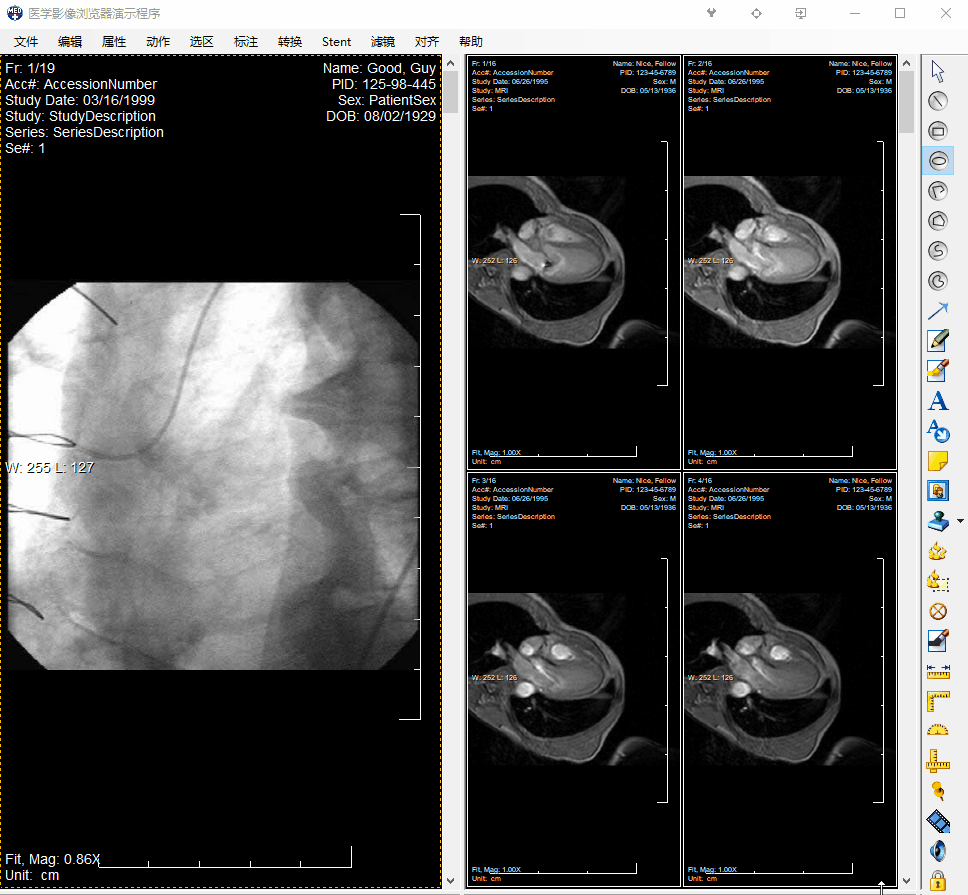

leadtools medical imaging sdk为.net(c# & vb.net)、winrt、html5、silverlight、wpf、c和c++开发者提供了许多dicom和影像标注选项,开发者可创建应用程序完成dicom、灰度、二值和彩色影像的标注。leadtools 医学影像和dicom标注可在不改变医学影像数据的基础上标注一个影像。

几个标注对象可存储为leadtools标注或转化为dicom标注并使用图形标注模块和灰度软拷贝表示状态iod存储在一个dicom数据集中。下面的对象可以在leadtools和dicom标注类型之间转换。

开发者和终端用户都能感受到leadtools标注的简单性。使用非常少的代码,开发者可以创建一个全自动的、动态的和功能丰富的标注应用程序,这个应用程序也容易被终端用户操作。自动化功能包括鼠标事件处理、游标、工具栏、右击快捷菜单和即时文本编辑。

使用leadtools?image annotation可定制功能,开发者可以创建新的标注类型、改变快捷菜单和工具栏并本地化对话框字符。终端用户可以旋转、调整和改变屏幕上标注的任意视觉设置。

增强的编校对象可以隐藏和加密医学影像的机密部分,甚至在非leadtools查看器中也可以。当和标注安全性结合起来后,这些编校对象提供了一种授予用户级别访问的方法,可以查看一个医学影像的绝密区域。